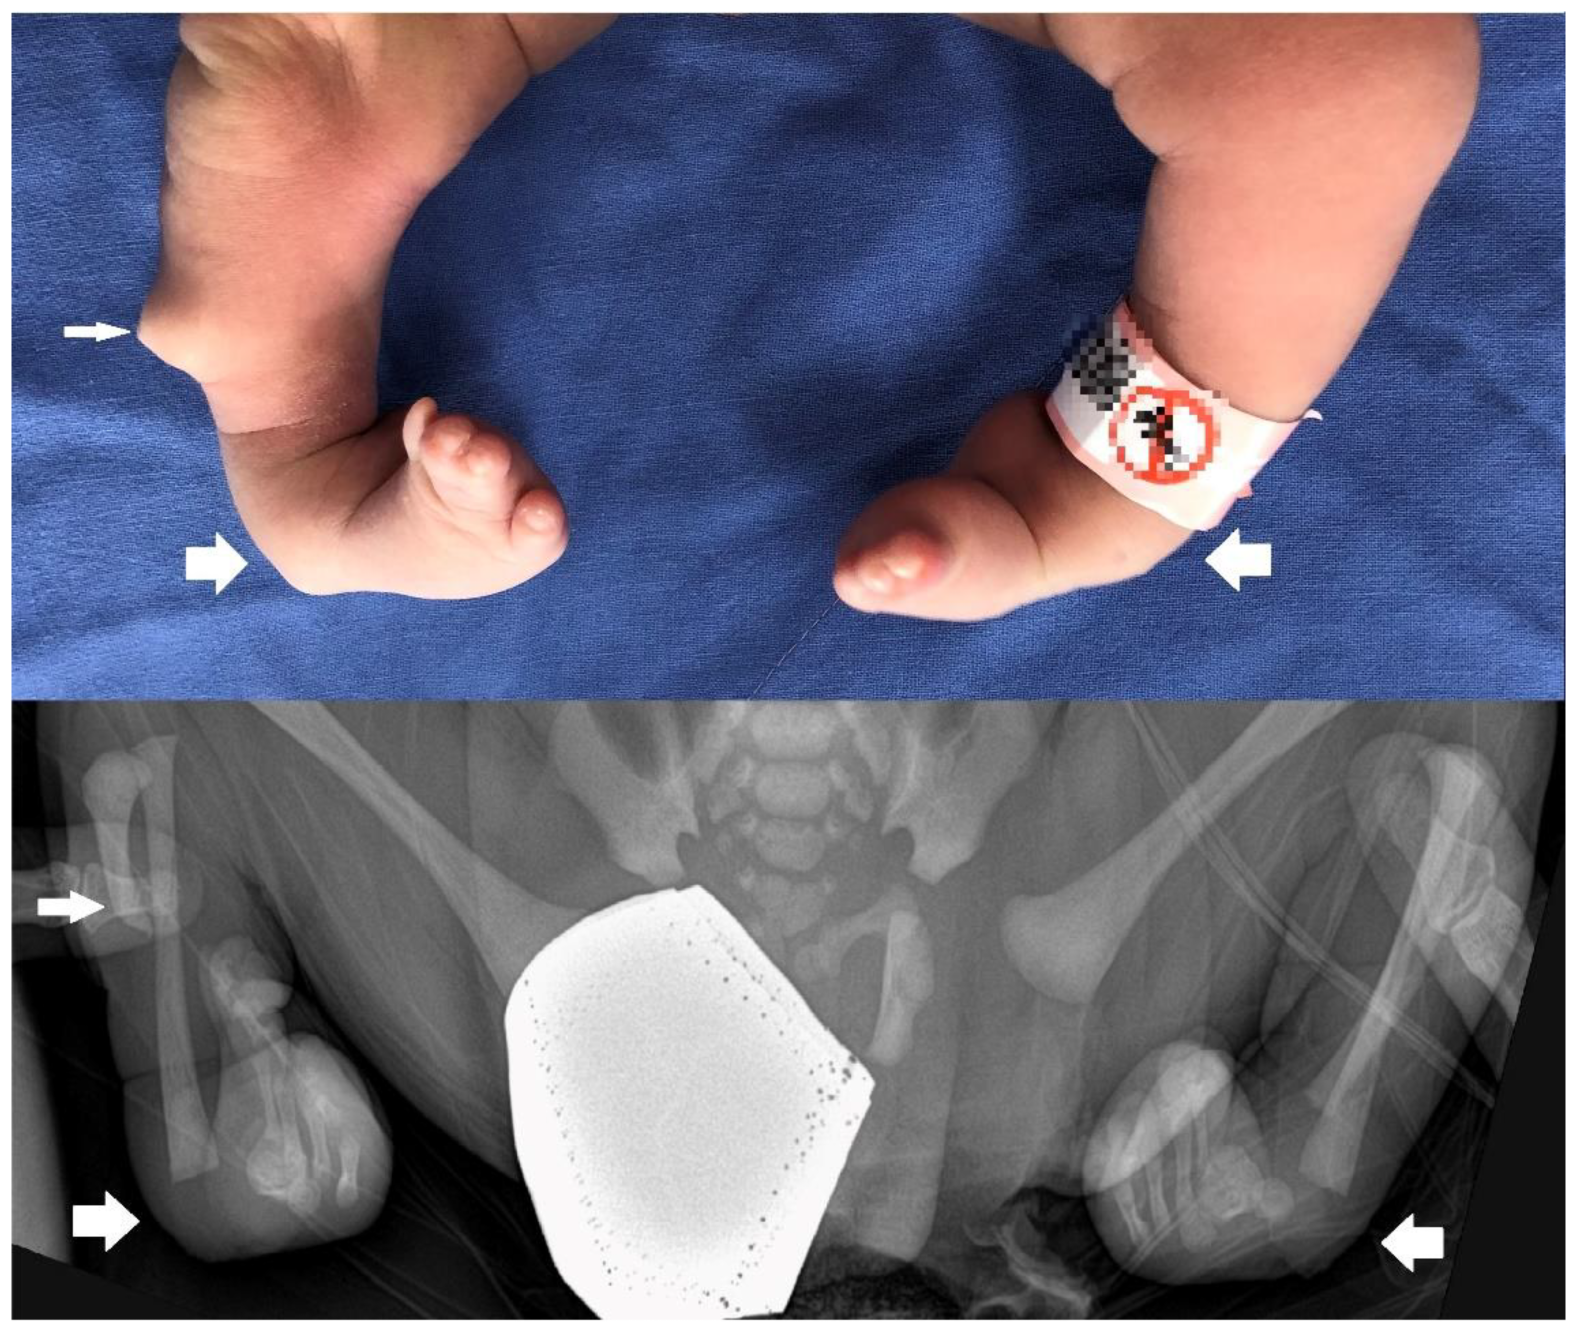

2. Detailed Case Description